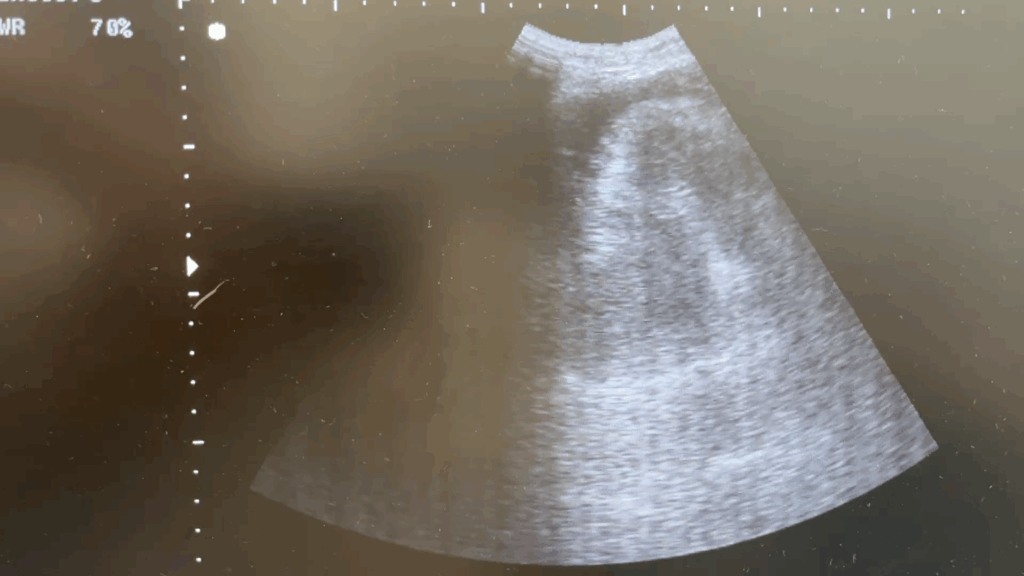

Con este material deberíamos ser capaces de poder realizar el abordaje inicial esta paciente, que se presenta al Servicio de Urgencias con motivo de consulta: Síncope.